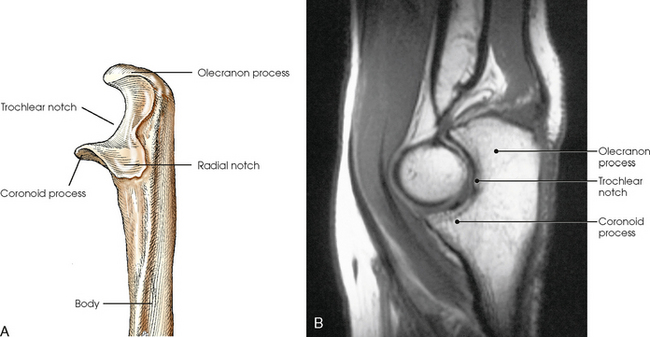

The carpals articulate with each other, the metacarpals, and the radius of the forearm. In the carpometacarpal (CMC) articulations, the first metacarpal and trapezium form a synovial saddle joint, which permits the thumb to oppose the fingers (touch the fingertips). The articulations between the second, third, fourth, and fifth metacarpals and the trapezoid, capitate, and hamate form synovial gliding joints. The intercarpal articulations are also synovial gliding joints. The articulations between the lunate and scaphoid form a gliding joint. The radiocarpal articulation is a synovial ellipsoidal type. This joint is formed by the articulation of the scaphoid, lunate, and triquetrum, with the radius and the articular disk just distal to the ulna (Fig. 4-9, C).